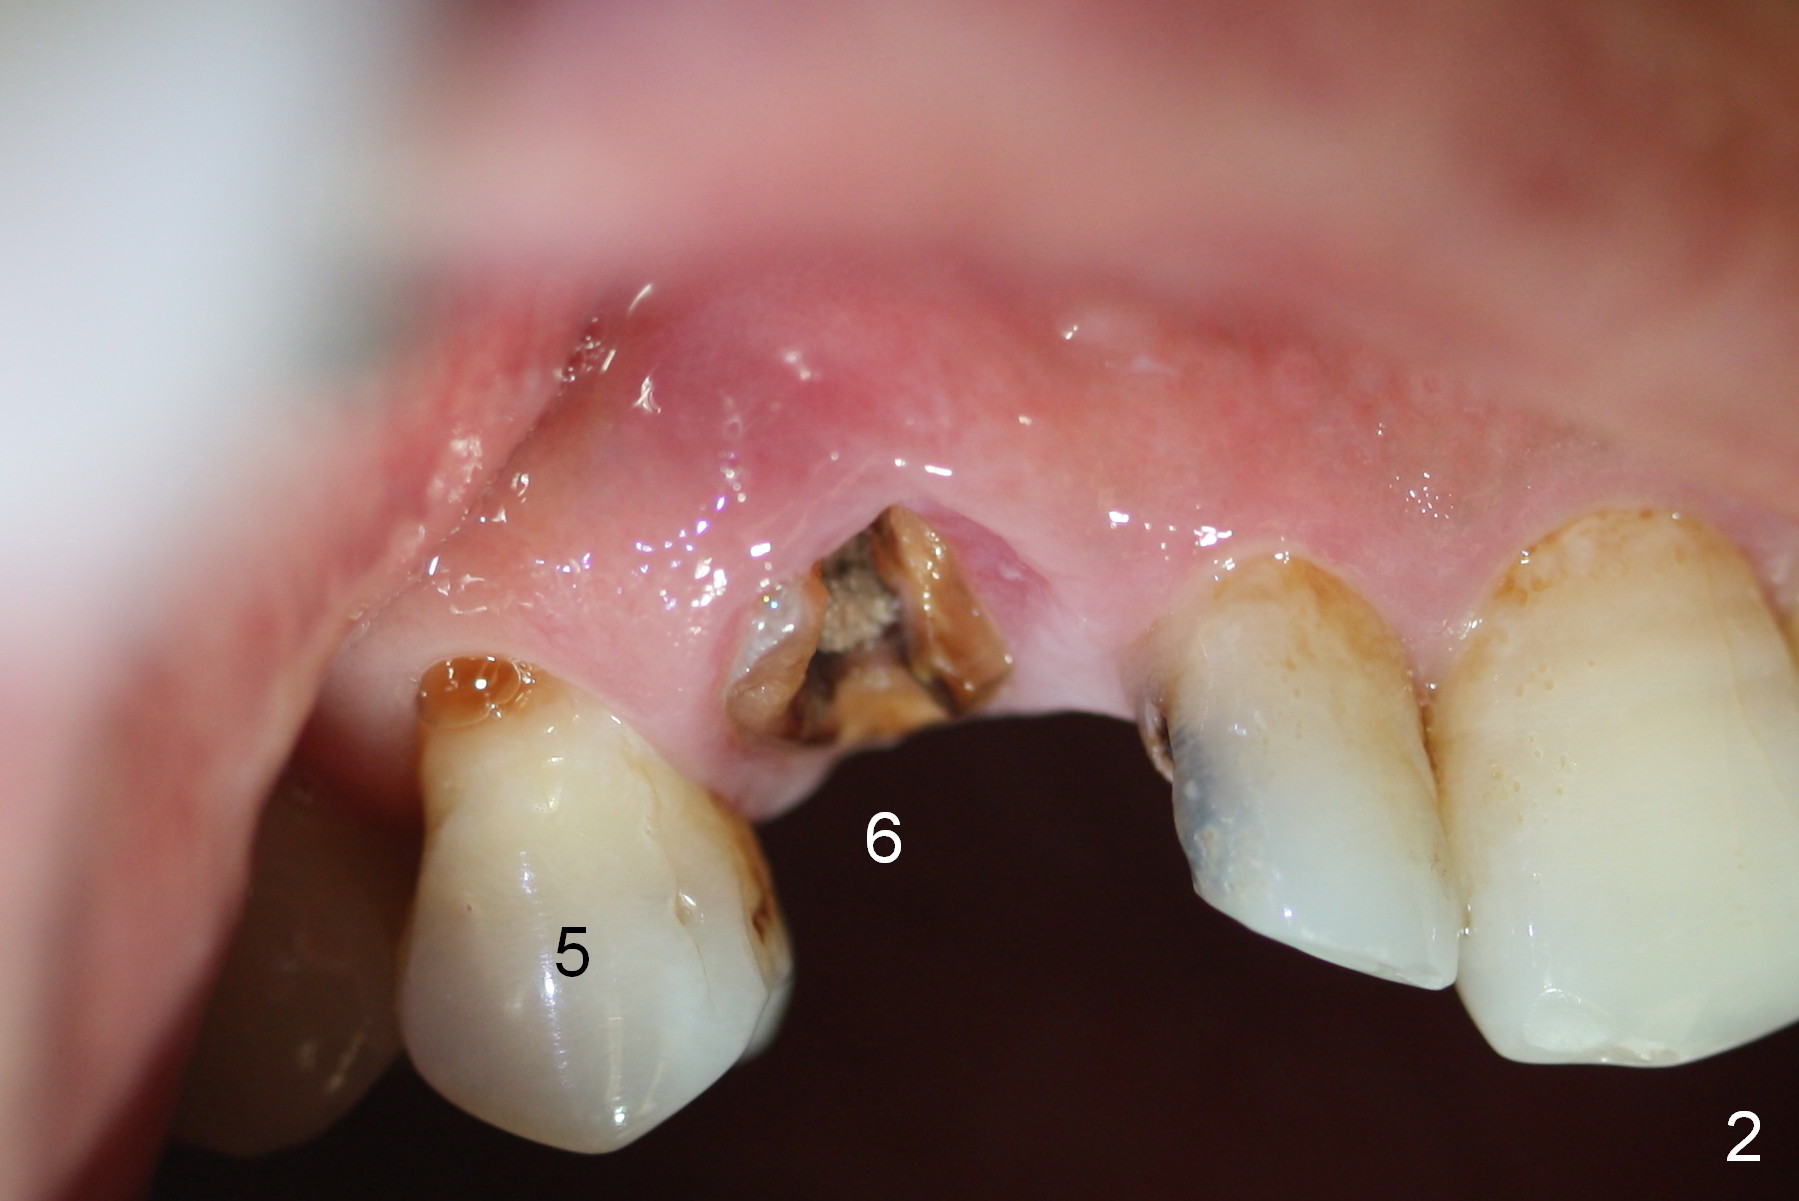

While the periodontal ligament is being severed with Proximators (periotomes), the tooth #6 is found closer to the tooth #5 (Fig.1,2). When the tooth is extracted, an osteotomy is initiated slightly mesially in the palatal wall of the socket (Fig.3 O).